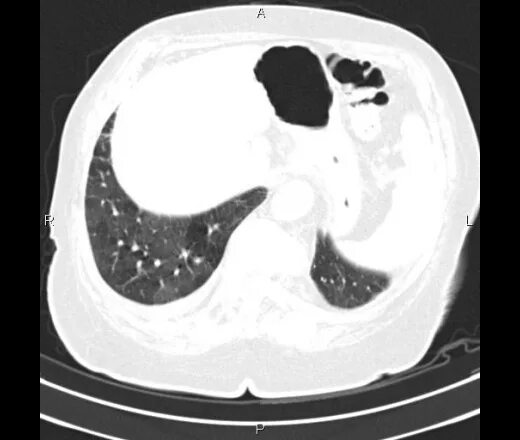

Мозаичная перфузия